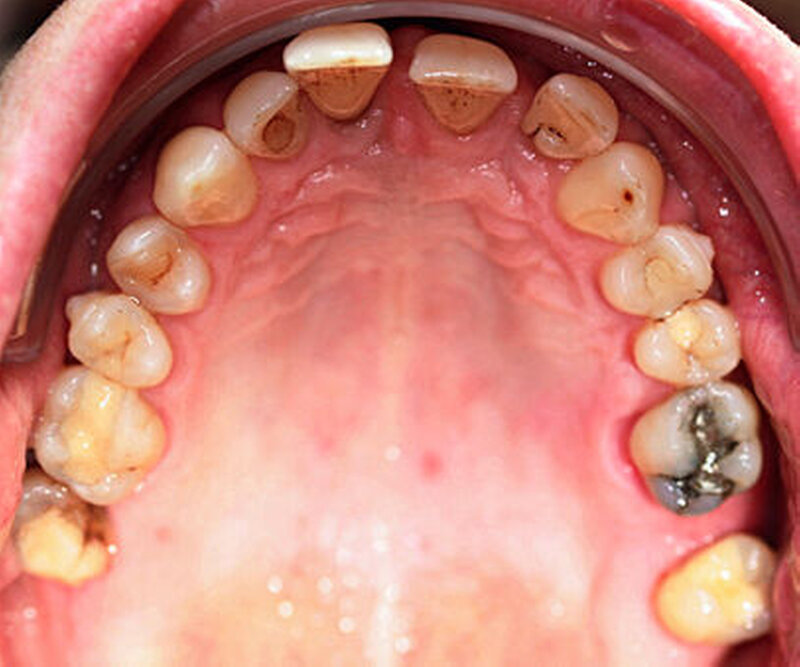

Röntgenologisch stellte sich im Orthopantomogramm der bereits intraoral ersichtliche horizontale und vertikale Knochenabbau mit Attachmentverlust an einzelnen Zähnen dar. Die Erhaltungswürdigkeit einzelner Zähne war aufgrund des starken Knochenverlustes beziehungsweise der Beeinträchtigung des Halteapparates als kritisch zu beurteilen.

Zudem wurde die Diagnose einer Parodontitis gestellt, die eine Rücküberweisung an den Hauszahnarzt erforderlich machte (Abbildung 2).